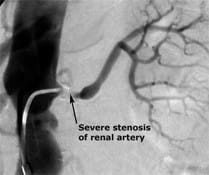

Renal artery stenosis is the narrowing of kidney arteries. This condition may cause high blood pressure and may eventually lead to kidney failure. Renal vein thrombosis means that you have a blood clot blocking a vein in your kidney. Blood clots in renal veins are uncommon and rarely affect the kidney, but they can sometimes travel to and lodge in arteries supplying your lungs, causing a dangerous condition called a pulmonary embolism.

Hardening of the arteries causes renal artery stenosis. Your arteries are normally smooth and unobstructed on the inside but, as you age, a sticky substance called plaque can build up in the walls of your arteries. Cholesterol, calcium, and fibrous tissue make up this plaque. As more plaque builds up, your arteries can narrow and stiffen. This is the process of atherosclerosis, or hardening of the arteries. Eventually, enough plaque may build up to interfere with blood flow in your renal arteries.